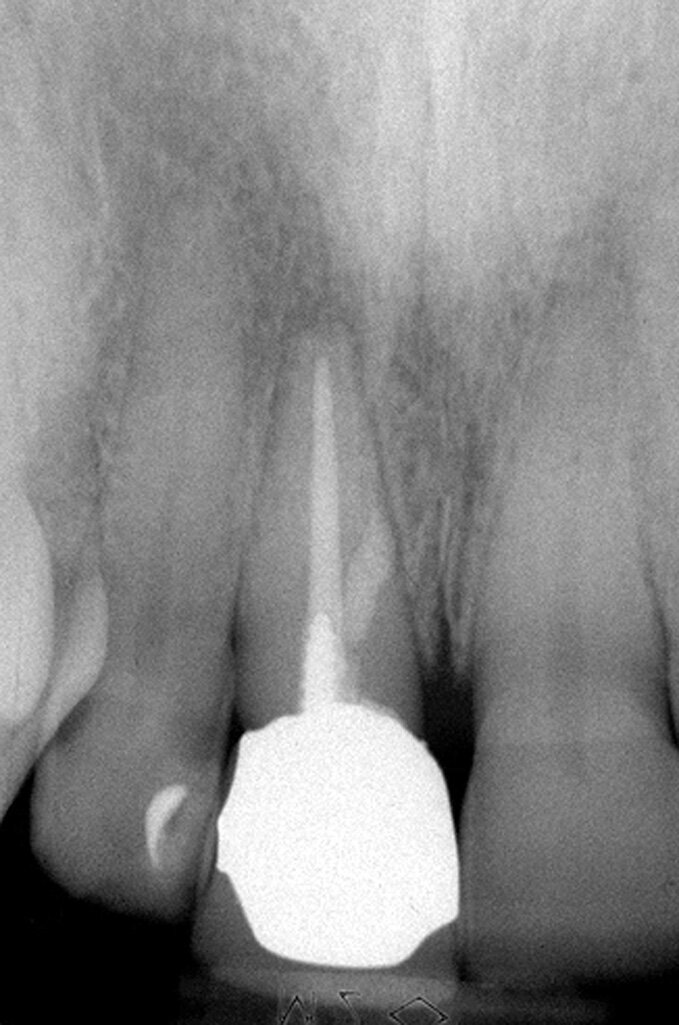

La sequenza operativa per sigillare una perforazione della radice o del pavimento di una camera pulpare è la seguente:

Prima visita

- Isolare il campo operatorio con la diga di gomma;

- Detergere la sede della perforazione con le comuni irrigazioni a base di ipoclorito di sodio e, se i margini della perforazione sono raggiungibili, con le punte da ultrasuoni;

- Nel caso di una contaminazione batterica, fare una medicazione con idrossido di calcio per una settimana;

- Applicare 2-3 mm di spessore di MTA;

- Controllare radiograficamente il corretto posizionamento del materiale;

- Applicare una piccola pallina di cotone bagnato a contatto con l’MTA;

- Posizionare il cemento provvisorio.

Seconda visita

- Isolare nuovamente il campo con la diga di gomma;

- Rimuovere il cemento provvisorio;

- Accertarsi dell’avvenuto indurimento dell’MTA;

- Completare la terapia.